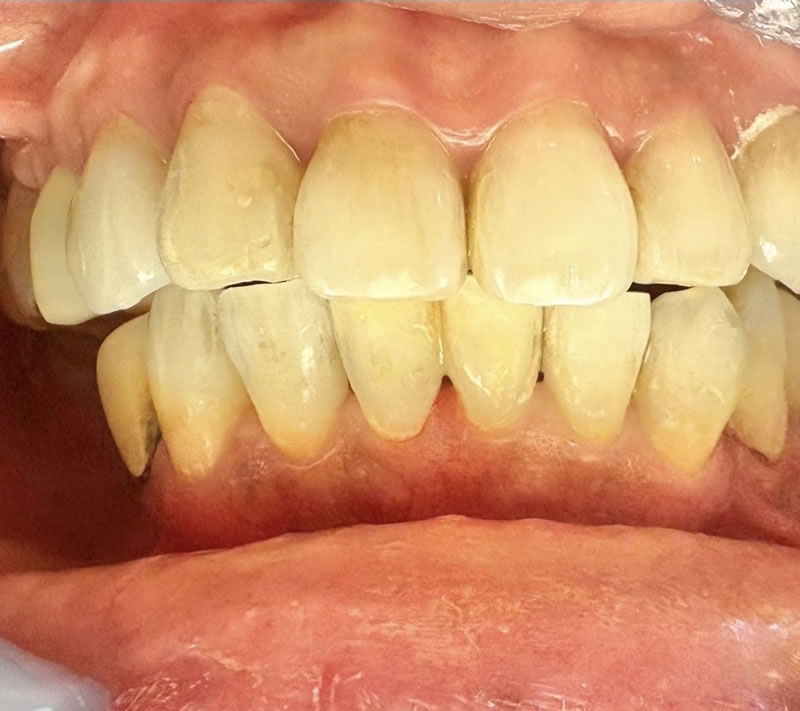

矯正後の60代後半女性で、下の前歯の歯茎下がりの空隙部位に食べものが入ってしまったり唾液が飛ぶから、封鎖したいという主訴でした。

ダイレクトボンディングによる歯の形態修正で足場を作り、ヒアルロン酸をキャリアにした幹細胞由来サイトカインとレーザーによる治癒促進治療による歯周組織再生誘導を同時に併用しました。